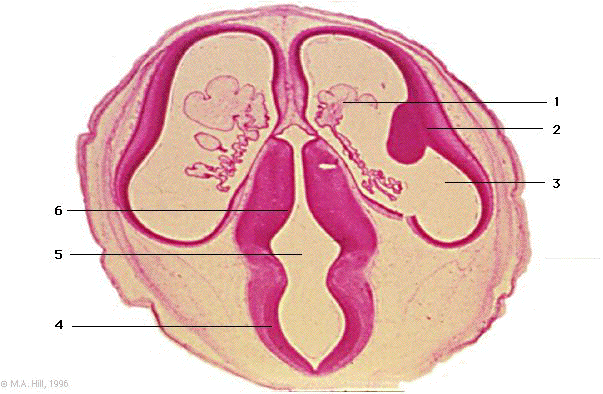

1

choroid plexus

2

telencephalon

3

lateral ventricle

4

mesencephalon

5

3rd ventricle

6

thalamus